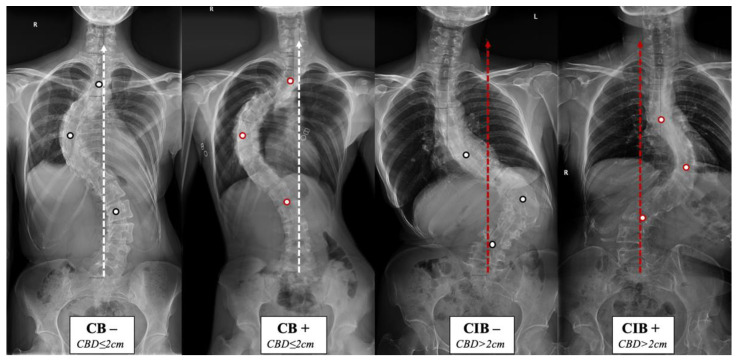

The lack of understanding of the natural history and compensatory mechanism of CB/CIB inspired us to propose the apical vertebras distribution modifier to supplement the CB classification for AdIS with a severe curve, which is defined as Cobb angle > 80 degrees in this study [ref. 7,ref. 8,ref. 9,ref. 10] (Figure 1 and Figure 2). A corresponding surgical algorithm is also proposed to address each type of coronal alignment. Surgical strategies were suggested in the algorithm according to the preoperative coronal classification to minimize the incidence of postoperative CIB.

The apical vertebras distribution modifier is proposed in this study to supplement the coronal balance classification based on the positional relationship between the centers of the apical vertebras (CoAVs) and the CSVL (Figure 1 and Figure 2). The apical vertebra modifier is defined as negative (−) when CoAVs are on either side of the CSVL. The apical vertebra modifier is defined as positive (+) when CoAVs are on the same side of the CSVL.

Therefore, we could categorize the patients into four groups, CB−/+ and CIB−/+. All patients were classified by the two attending surgeons according to the classification method described above. The interval between the two classifications was 1 week. In addition, for cases in which the two observers held different classification opinions, a third observer, a senior spine surgeon, was involved in joint judgment and to determine the final classification. The consistency of classification was judged based on the Kappa value of the consistency test.